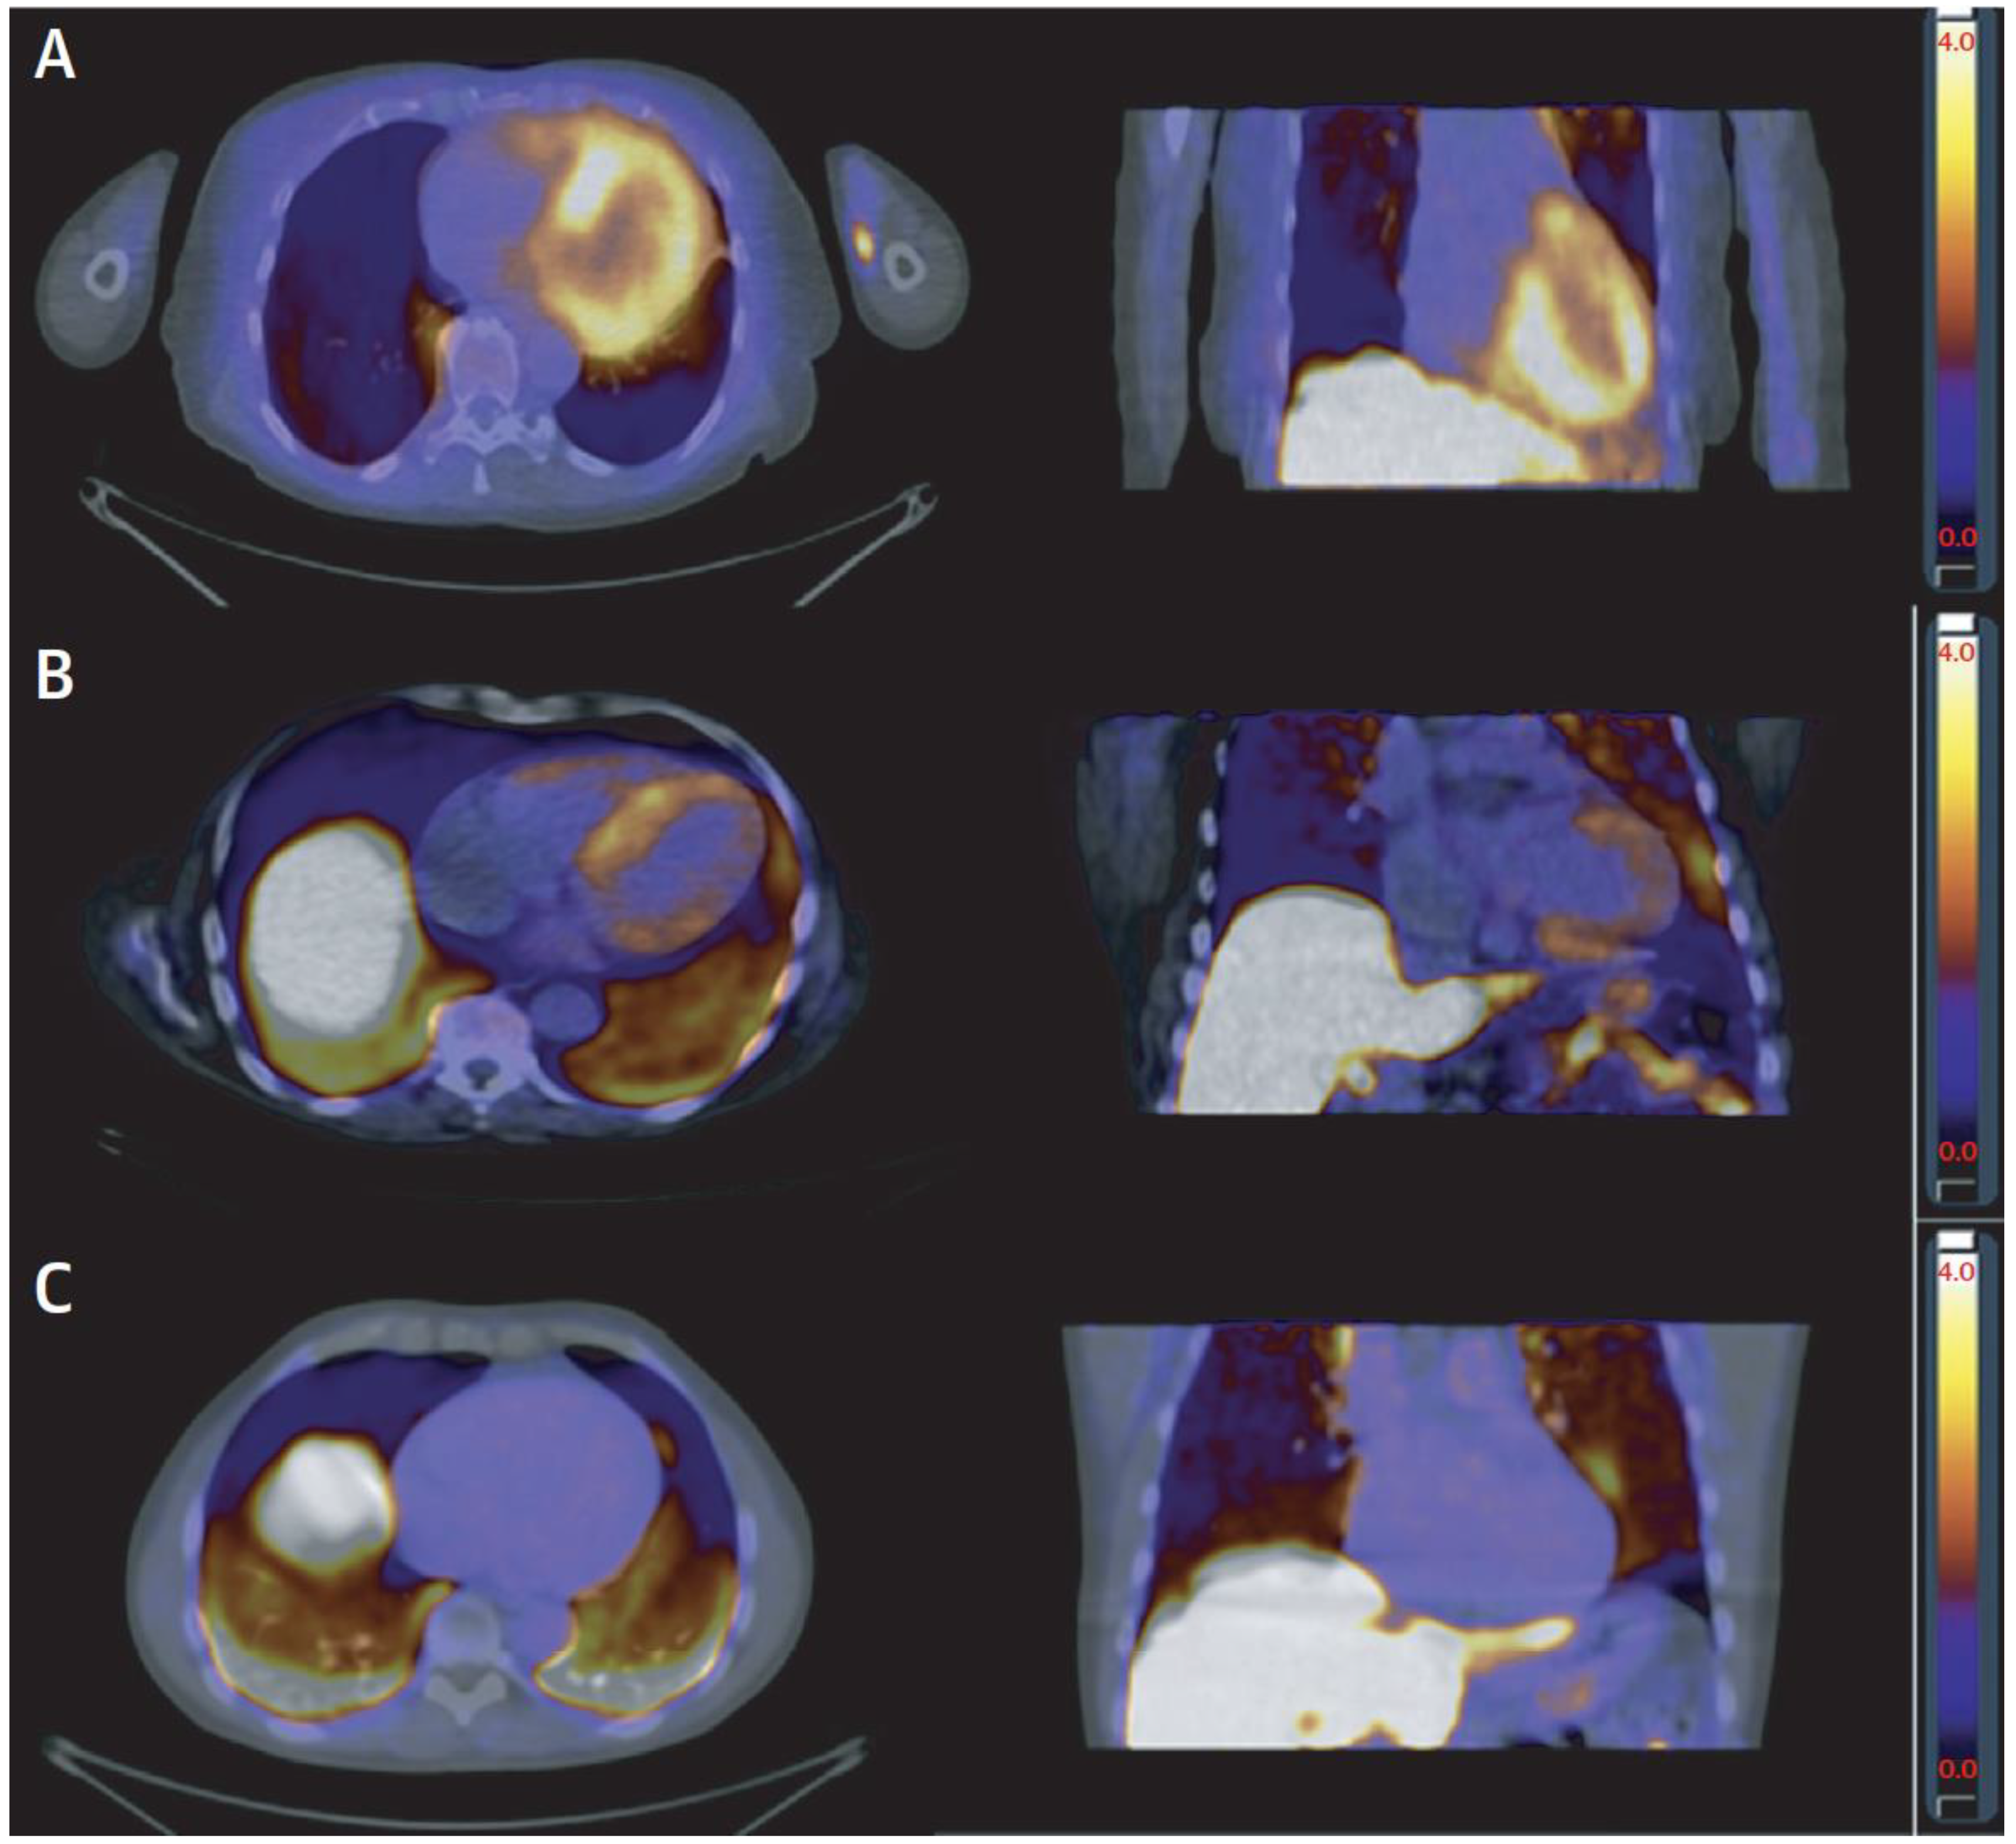

7. Myocardial Perfusion

| Nuclear Perfusion Imaging | Assessment of myocardial perfusion (coronary or microvascular disease); assessment of amyloidosis with specific tracers; sarcoidosis | PET is gold standard for myocardial perfusion; identification of perfusion/metabolism mismatch, as in hibernating myocardium; high accuracy for amyloidosis and sarcoidosis; DPD imaging (planar/SPECT) is sensitive for cardiac ATTR amyloidosis | PET limited to centers with cyclotron; radiation exposure |